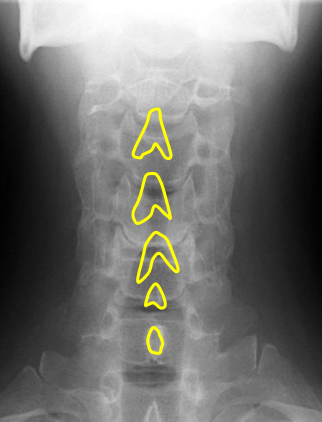

Vertebral bodies

Superior and inferior endplates

Disc space

Mandible

Hyoid bone

Mitchel marker

Occipital condyle

C1 anterior tubercle

C1 posterior arch

Odontoid process

Atlanto-Dental interspace

C1 lateral masses

Uncinate processes

Inferior aspect of vertebral bodies

Junction of laminae

Pedicle shadows

Vertebral waist

Inferior endplate tips

Superior endplate tips